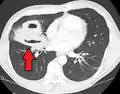

Pulmonary abscess on CT scan

Lung abscesses are often on one side and single involving posterior segments of the upper lobes and the apical segments of the lower lobes as these areas are gravity dependent when lying down. Presence of air-fluid levels implies rupture into the bronchial tree or rarely growth of gas forming organism.